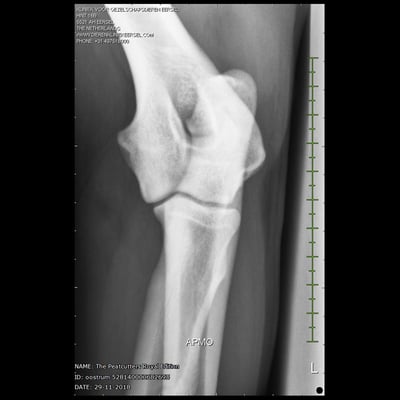

Sjors his official hip and elbow results with the photos. X-rayed at 20 months of age. HD-C, ED-0.